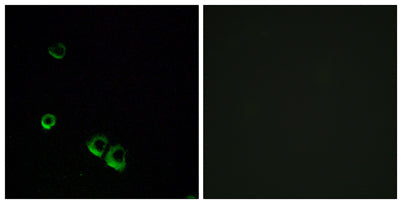

AVP Receptor V2 rabbit pAb